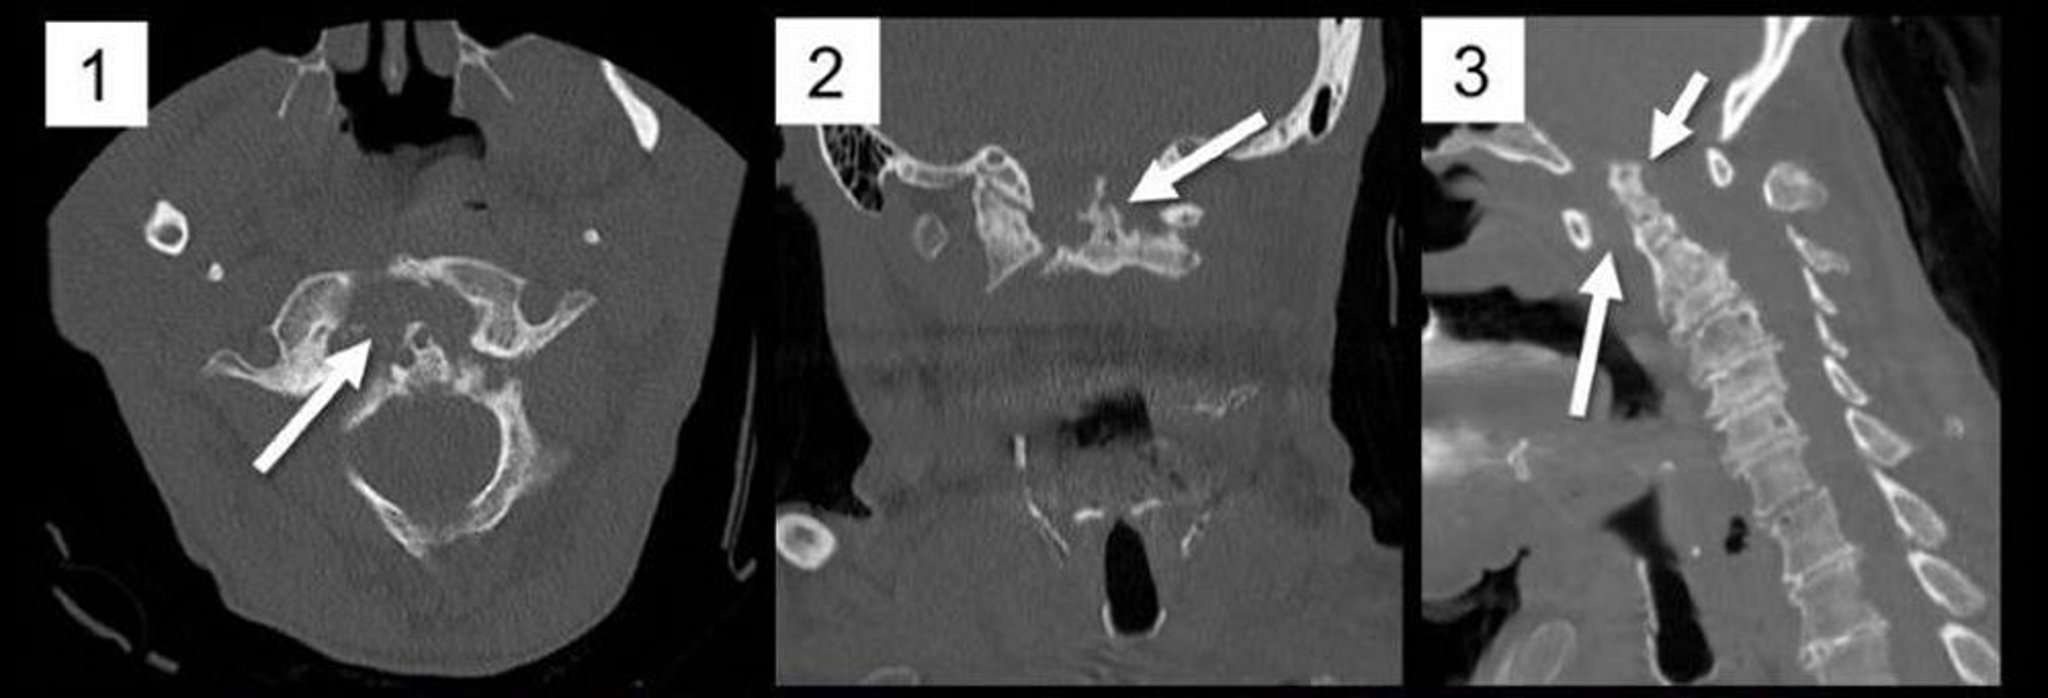

Sublussazione atlanto-assiale (TC)

Le ricostruzioni multiplanari di una TC della colonna cervicale nei piani assiale (1), coronale (2) e sagittale (3) mostrano un marcato allargamento dell'intervallo atlantodentale anteriore secondario alla formazione del pannus come avviene nell'artrite reumatoide (1, freccia; 3, freccia lunga), causando una sublussazione posteriore e un'impressione basilare del processo odontoideo C2 (3, freccia corta). Il processo odontoideo è marcatamente eroso (2, freccia), un tipico reperto nell'artrite reumatoide.

Image courtesy of A. John Tsiouris, MD.